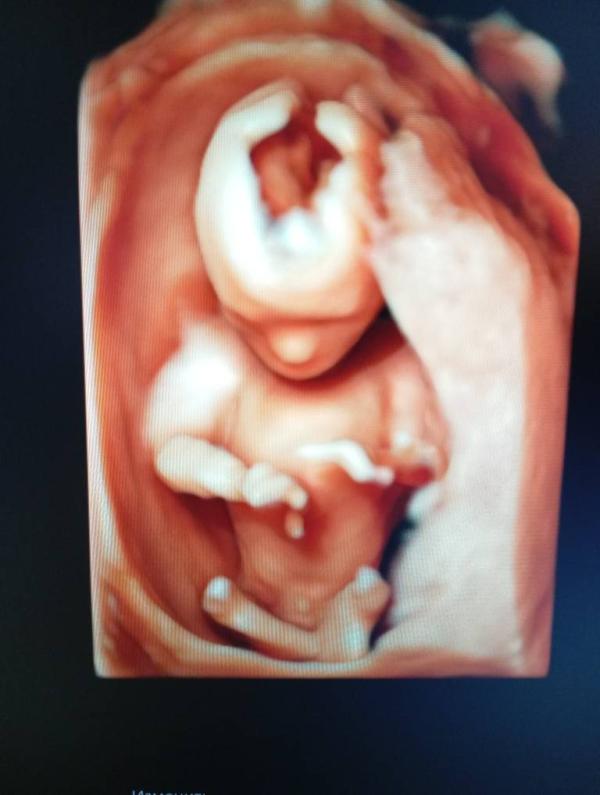

Кто определит пол?

Девочки , Кто сможет определить пол?

Во как хорошо видно . Мальчик ведь

На обоих снимках

Мальчик это

@mamalab95 вот здесь точно видно писюн👍

Видно же что мальчик